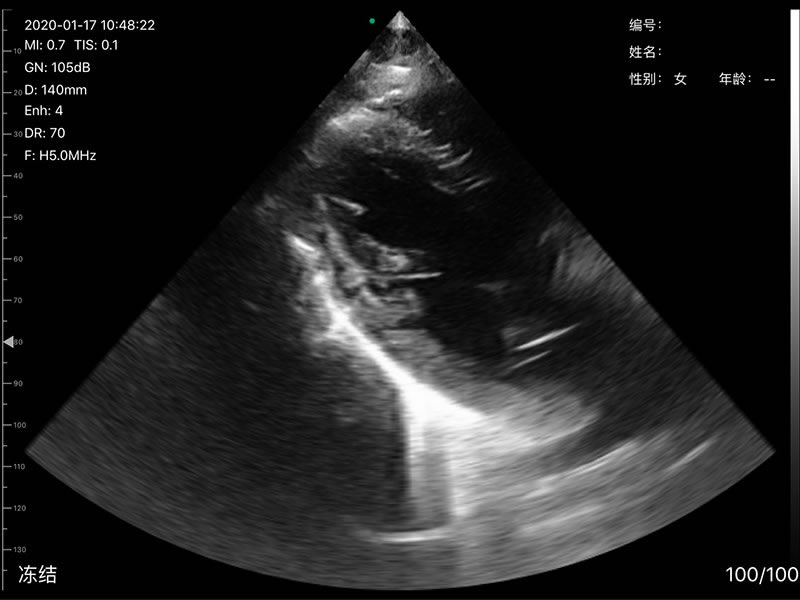

• 探头频率:相控阵2.2/3.6MHz,线阵7.5/10 MHz

• 扫描深度:相控阵20-240mm,线阵 20-100mm,可调

• 显示模式:B、B/M、Color、PW、PDI